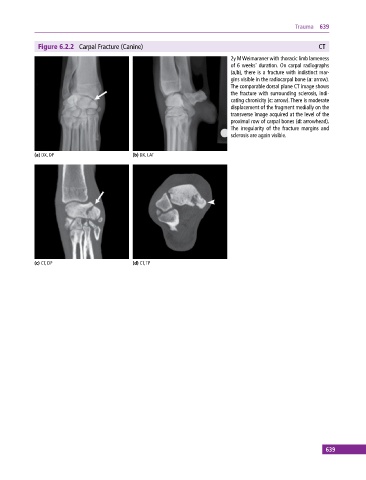

Figure 6.2.2 Carpal Fracture (Canine) CT

2y M Weimaraner with thoracic limb lameness

of 6 weeks’ duration. On carpal radiographs

(a,b), there is a fracture with indistinct mar-

gins visible in the radiocarpal bone (a: arrow).

The comparable dorsal plane CT image shows

the fracture with surrounding sclerosis, indi-

cating chronicity (c: arrow). There is moderate

displacement of the fragment medially on the

transverse image acquired at the level of the

proximal row of carpal bones (d: arrowhead).

The irregularity of the fracture margins and

sclerosis are again visible.

(a) DX, DP (b) DX, LAT

(c) CT, DP (d) CT, TP